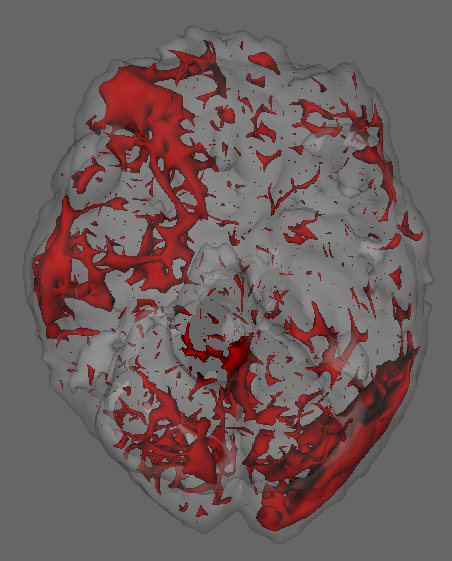

This dataset is due to Wakeman & Henson (2015), where each of the 19 subjects go through 9 runs of consecutive visual tasks. Blood oxygen level readings are recorded across time as 3D images made of (total 135,168) voxels. Here we use the data from a single run and task on subject 1, and aim to estimate dependence patterns of readings across 210 time points and areas of the brain.

We fit separate regressions at each voxel (Appendixย E), with second order autoregressive terms, neighboring voxel readings and one-hot encoded visual task categories in the design matrix. After applying the e-value feature selection, we compute the F-statistic at each voxel using selected coefficients only, and obtain their p-values. Fig.ย 7.1c highlights voxels with p-values . Left and right visual cortex areas show high spatial dependence, with more dependence on the left side. Signals from the right visual field obtained by both eyes are processed by the left visual cortex. The lop-sided dependence pattern suggests that visual signals from the right side led to a higher degree of processing in our subjectโs brain. We also see activity in the cerebellum, the role of which in visual perception is well-known (Calhoun etย al., 2010; Kirschen etย al., 2010).

Appendix E Details of fMRI data implementation

Typically, the brain is divided by a grid into three-dimensional array elements called voxels, and activity is measured at each voxel. More specifically, a series of three-dimensional images are obtained by measuring Blood Oxygen Level Dependent (BOLD) signals for a time interval as the subject performs several tasks at specific time points. A single fMRI image typically consists of voxels in the order of , which makes even fitting the simplest of statistical models computationally intensive when it is repeated for all voxels to generate inference, e.g. investigating the differential activation of brain region in response to a task.

The dataset we work with comes from a recent study involving 19 test subjects and two types of visual tasks (Wakeman & Henson, 2015). Each subject went through 9 runs, in which they were showed faces or scrambled faces at specific time points. In each run 210 images were recorded in 2 second intervals, and each 3D image was of the dimension of , which means there were 135,168 voxels. Here we use the data from a single run on subject 1, and perform a voxelwise analysis to find out the effect of time lags and BOLD responses at neighboring voxels on the BOLD response at a voxel. Formally we consider separate models at voxel , with observations across time points .

Clubbing together the stimuli, drift, neighbor and autoregressive terms into a combined design matrix and coefficient vector , we can write . We estimate the set of non-zero coefficients in using the e-value method. Suppose this set is , and its subsets containing coefficient corresponding to neighbor and non-neighbor (i.e. stimuli and drift) terms are and , respectively. To quantify the effect of neighbors we now calculate the corresponding -statistic:

and obtain its -value, i.e. .

Figureย E.1 shows plots of the voxels with a significant -value from the above -test, with a darker color associated with lower p-value, as opposed to the smoothed surface in the main paper. Most of the significant terms were due to the coefficients corresponding to neighboring terms. A very small proportion of voxels had any autoregressive effects selected (less than 1%), and most of them were in regions of the image that were outside the brain, indicating noise.